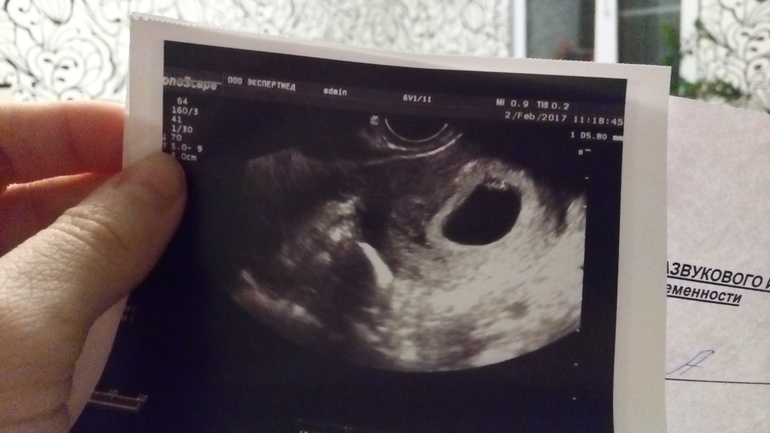

У меня на сроке 5 акуш. Нед (3 эмбр.) было только плодное яйцо 7 мм.

У меня тоже 4нед 6 дней и плодное яйцо 7,7мм )

Плюсую.А вот на узи у меня увидели только на 6-7 неделе

И у меня на 7й! Такая манюня) 5 нед и 2 дня по зачатию

Ой блин. Не дописала... в 2.5 недели нет никакого эмбриона! Только пя. Эмбрион точно увидят на 6-7 неделе. Не бегайте на узи и не делайте тесты, наберитесь терпения!!! Скоро все хорошо будет видно))) я на 5 неделе была на узи, поставили 4 недели, пя только было. В 8 недель уже хороший эмбриончик, в 11 человечек))) так что не переживайте) все хорошо у Вас!!!

У меня 5 акушерских было, 4 эмбриональные на первом узи.

Наберитесь терпения, все у вас будет хорошо! Ещё увидите и не раз своего ребетеночка )) На таких ранних сроках лучше на УЗИ не ходить, только нервы себе расшатаете. Не видно там ещё особо ничего. Хотите поромониторить, лучше ХГЧ в динамике сдать. А на УЗИ в 6-8 недель.

пол ребёнка на первом УЗИ скрининге? третья беременность завтра 11 неделька пойдёт)